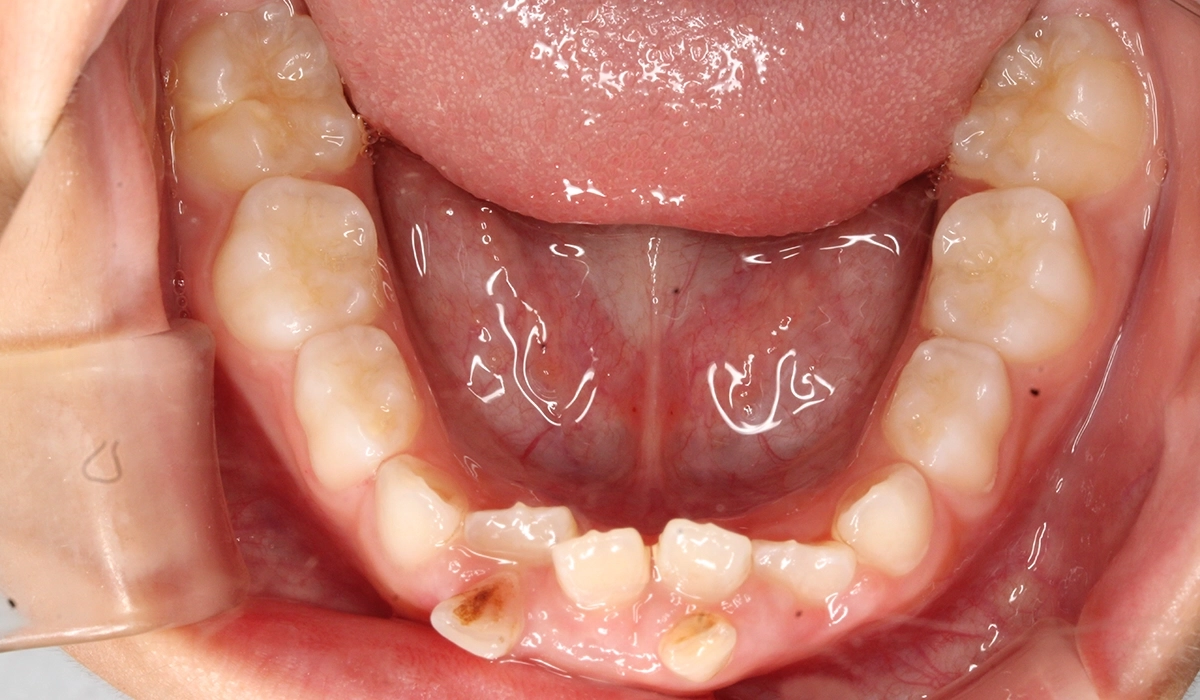

術前:下顎

術後:下顎